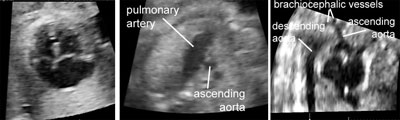

Complete transposition of great arteries

Legend:Complete transposition of great arteries: two great vessels arise in parallel fashion from the base of the heart without crossing; the posterior vessel connected to the left ventricle bifurcates and can therefore be positively identified as the pulmonary artery; the anterior vessel arising from the right ventricle has a long upward course and is the aortic arch

Interrupted aortic arch

Legend:Interrupted aortic arch: there is ventricular disproportion and the ascending aorta is not connected to the descending portion